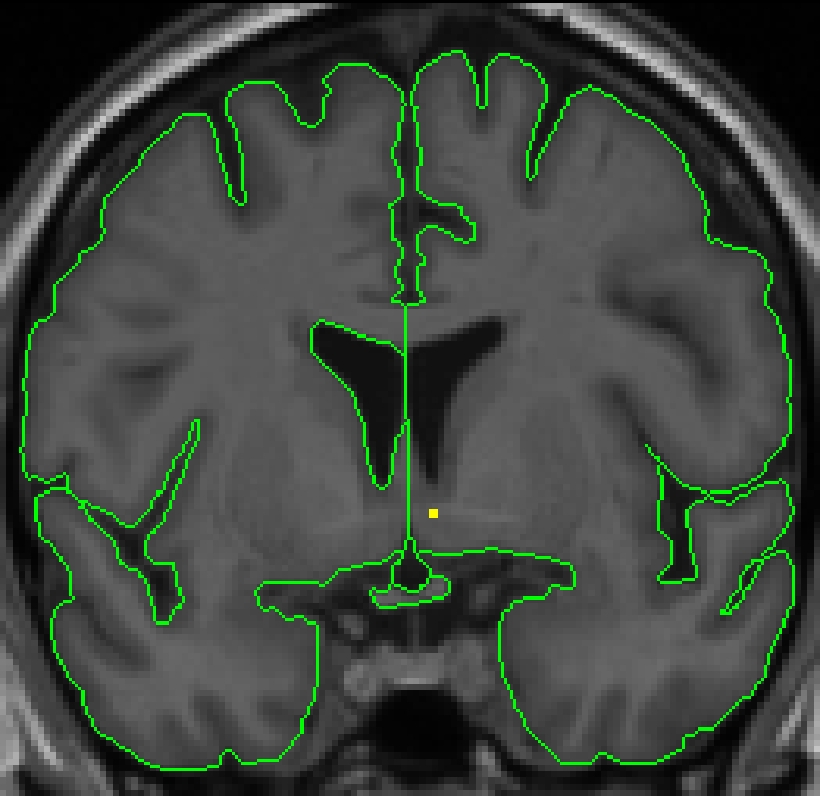

Part III - Posterior portion of lateral ventricle

Make sure the lateral ventricle is actually a ventricle, rather than a deep

sulcus. To do this, look in other planes using the projection lines. There

should be white matter between ventricle and the gray matter. Lateral ventricle

can disappear for a few slices, and then re-appear.